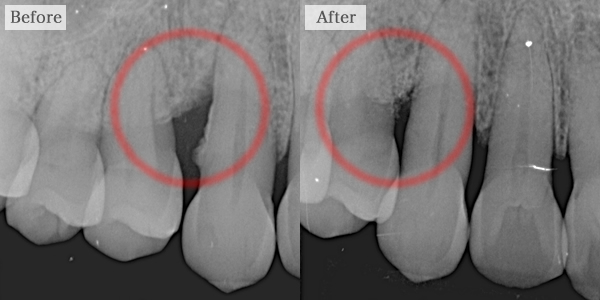

クラウンレングス二ング

歯が虫歯によって歯肉に被っています。

被っていると土台をたてる事が難しいため、精密な治療ができないもしくは、最悪の場合抜歯になる可能性もあります。

歯肉を下げることによってより良い環境で型をとることができます。

また、抜歯となる歯を救うこともできる可能性があります。